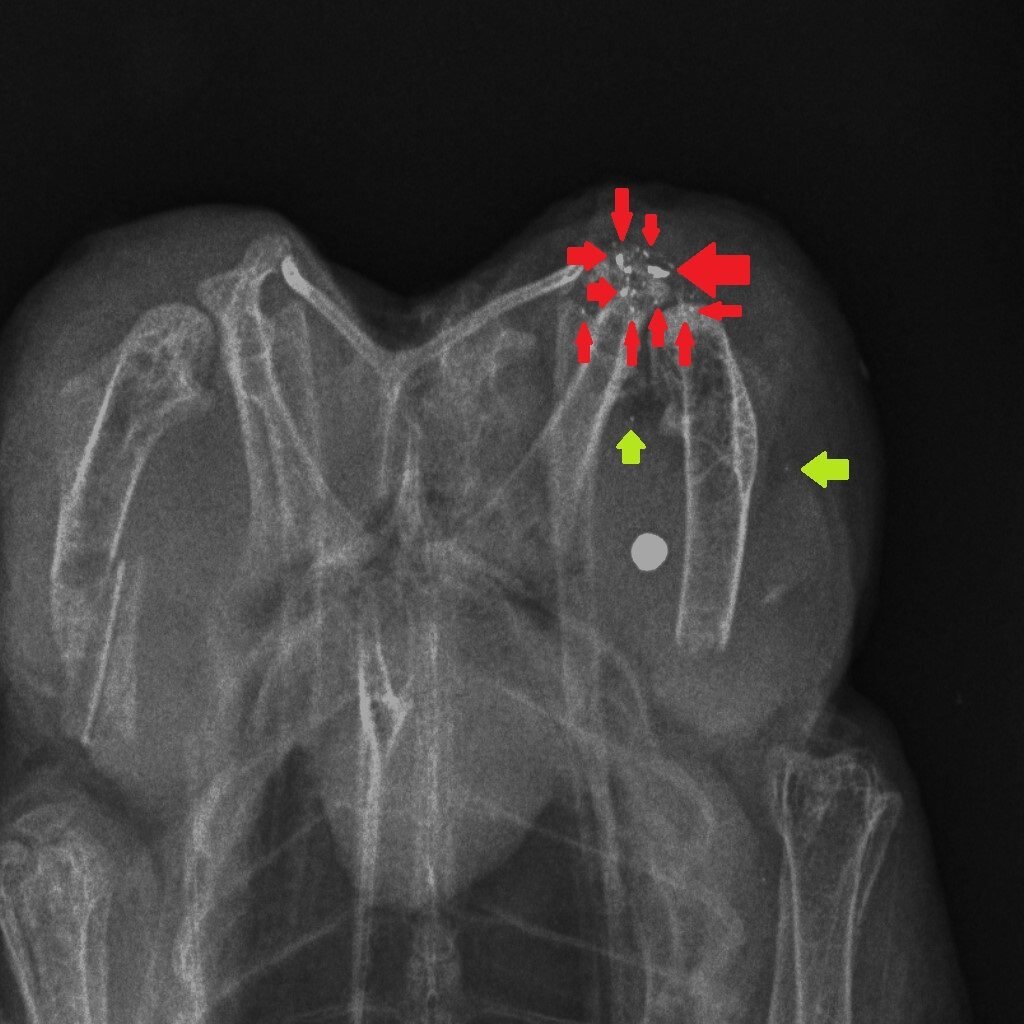

How could we reduce the risk of exposure to lead in game meat? It’s simple – stop shooting lead ammunition into animals that are destined for the human food chain. One of the useful properties of lead is that it is soft and malleable – that’s why, in the past, we have used it widely. But those same physical properties mean that lead passing through the flesh of a shot animal, hitting organs, soft tissue, bones and cartilage, shatters and tiny fragments of lead spread through the body of the animal. Here are three x-rays of shot birds that were bought in butcher’s shops and then x-rayed. The top x-ray is of a partridge and the other two are Red Grouse. Large white circular objects are lead shot. The green arrows point to fragments of bone and the red arrows indicate fragments of lead, from the shot, that have spread through the flesh.

Almost all of the fragments of lead are tiny – far too small to be detected in the cooking or eating process. Yes, you can spit out the almost-intact lead shot but you can’t get rid of the fragments. The lead analyses that have been done in studies cited above, and in our own, remove the lead shot and analyse the lead content of the meat after that removal. So when Sainsbury’s say that their game meat has no lead shot in it that’s good (although careful eating would remove those anyway) but they are not removing the tiny fragments of lead. So removing the almost intact lead shot particles is pretty irrelevant to the lead levels in the meat, as we will show you later this week…